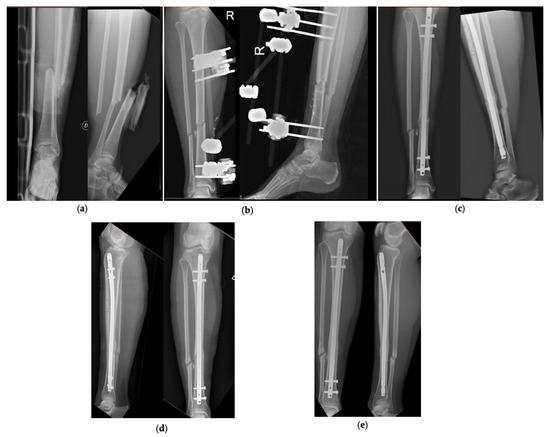

Figure 2 and Figure 3 show 2 clinical cases of the series, with pre-operative and follow-up radiographic images.

Figure 3.

Patient number 31 of the series. (a) Pre-operative AP and LL X-rays, (b) AP and LL X-ray after application of the external fixator, (c) AP and LL X-rays at 3 months, (d) AP and LL X-rays at 6 months, (e) AP and LL X-rays at 12 months.